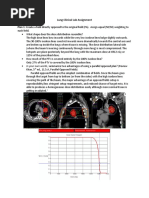

The above image displays the plan without any correction. The patient is a homogenous, uniform

density – that of water. The tumor volume is outlined and shaded in pale green. The position of

the lungs are outlined in blue and yellow. The dose has been normalized to the isocenter – the

100% isodose line in red is visibly running through this point. The Dmax depth for 6MV is

approximately 1.5cm – and at both beam entry points within the patient, there are areas of higher

dose – over 107%. This is the region of electronic equilibrium. The lower isodose lines, <90%,

follow close to the beam edge throughout the treated volume. As the patient is of a uniform,

medium density, there is adequate scatter forward and laterally to maintain electronic

equilibrium. The only dose variation that we see – highlighted in the axial and sagittal views – is

with the higher isodose lines, 95% and 100%. They are bowing in centrally, and seem tilted

towards the patient’s right side. They also bow in inferiorly. This is not due to any

inhomogeneity, this is because the patient separation increases left-right and superiorly-

inferiorly. The more material a beam traverses, the more attenuated it becomes. This is similar to

the effect seen when a beam traverses high density materials. The effective path through higher

density materials is greater than the same length of lower density materials because of the

increased electron density (g/cm3). In this plan, the tumor coverage appears to be relatively good,

with 100% of the volume receiving 95% of the dose, as visualized in the dose-volume histogram

(DVH) below. The mean dose throughout the tumor volume is 100.3%.